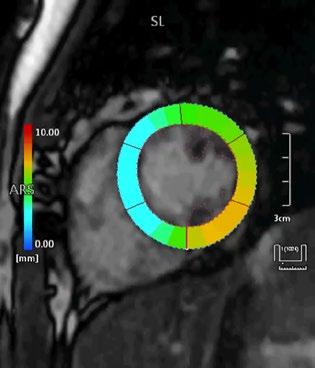

Fig 1: Next generation MRI is being used to gather data on brain tissue volumes Dr. Steve McNally

From this season at Manchester United Football Club, we have started to gather data by using MRI (see fig 1) to measure volumes of brain tissue in specific areas, to monitor for a decrease in volumes over time. If the volumes become unusual or deviate from the norms that we would expect, it may help us identify early changes of CTE that need closer monitoring. This is a new, long-term data gathering study in our cohort of players that has been facilitated with the new next generation MRI3 now in place at our medical centre.